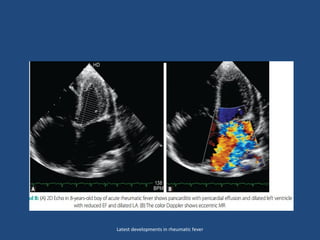

Echo features of carditis

• M-mode features are:

• (1) LA,LV-are dilated, LA:AO ratio is altered.

• (2) Thickened mitral/aortic/tricuspid leaflets more than or

equal to 4 mm (normal less than or equal to 3 mm).

• 2D Echo: EDV,ESV-increased and ejection fraction may or may

not be reduced. EF reduction is never severe in ARF

• In ARF edematous valve>4mm –seen in 93.6% cases

• Increased echogenicity of submitral apparatus –PLAX view

• Physiological versus pathological M.regurgitation:

pathological valvular regurgitation can be easily differentiated

from physiological regurgitation by :

• Substantial color jet in 2 planes extending well beyond

thevalve

• Color jet of MR passes over the posterior wall of LA. It is a

high velocity signal in pulse Doppler, with a well defined,

dense, high velocity spectral envelope with holosystolic MR.